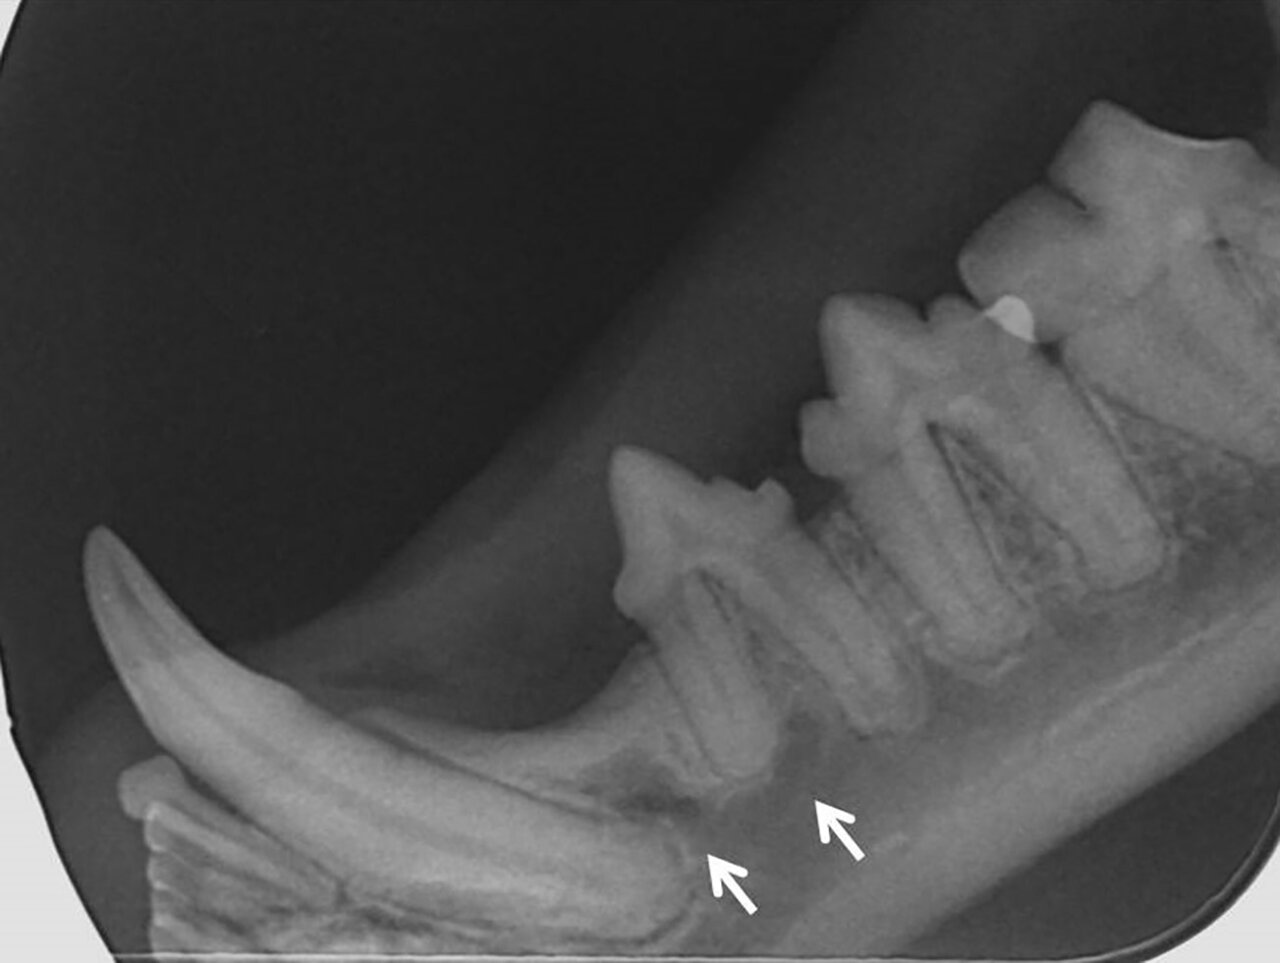

Para el diagnóstico de la EP, además de realizar un examen periodontal a través del sondaje debemos apoyarnos en la radiografía, ya que nos proporciona información acerca de la cantidad de pérdida ósea existente, así como del patrón que sigue esta pérdida (horizontal y/o vertical). En dientes multirradiculares, podemos servirnos de la furca para evaluar la pérdida de hueso, ya que aparecen áreas radiolúcidas bajo la bifurcación radicular a medida que se produce la destrucción ósea.

De acuerdo a esta pérdida del hueso alveolar detectada a nivel radiológico, clasificaremos la EP en cuatro grados:

- Grado 1 (PD1): sin pérdida ósea.

- Grado 2 (PD2): pérdida del soporte óseo menor al 25 % (imagen 7).

- Grado 3 (PD3): pérdida del soporte óseo de un 25-50 % (imagen 8).

- Grado 4 (PD4): pérdida del soporte óseo mayor de un 50 % (imagen 9).

Además de permitirnos evaluar el grado de enfermedad periodontal, también hace posible seleccionar el mejor tratamiento en función de su patología y las posibles complicaciones, como las fracturas mandibulares iatrogénicas en perros de talla pequeña con enfermedad periodontal PD4 (imágenes 10 y 11).